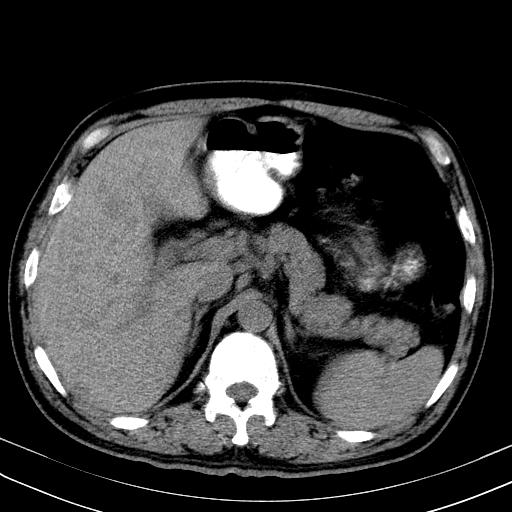

先行ct平扫,纵膈内多发软组织影,ct值约为36hu,以下为增强扫描和腹部平扫。

经典?纵膈多发肿大淋巴结。腹膜后未见异常。

还见胃窦壁增厚!转移亦有可能!

1)考虑淋巴瘤。2)双侧少量胸腔积液。

大家看看肝脏右叶片状低密度影是什么改变啊?

淋巴瘤?肝脏请增强后说啊

多发肿大淋巴结影,肝内改变需结合强化观察